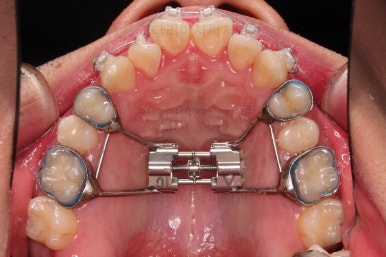

우선은 악궁확장장치를 합니다.

악궁확장은 언제 해야 되는가? 성인은 모두 미니스크류를 이용해야 하는가?(MARPE?)

악궁확장은 단순히 윗니가 삐뚤다고 하는 것도 아니고, 주걱턱이라고 하는 것도 아닙니다.

아래턱에 비해서 위턱이 좁을 때 하는 것이고요.

성인이라고 모두 미니스크류를 이용한 악궁확장장치(MARPE)를 하는 건 아니며, 여러 가지 분석법으로 성인에서도 일반 악궁확장장치(RPE) 성공 가능성이 높은 환자분은 일반 확장장치를 사용하고 있습니다.

(이 부분은 부산긴얼굴긴턱교정 키다리아저씨치과 석사 논문 써서 SCI저널에 게재 되었던 내용이기도 합니다. ^^)

아무튼 이번 환자분은 위턱 자체가 폭이 좁아서 확장을 먼저 진행했고요.

확장 이 후 유지 기간동안 다른 치열을 가지런하게 해줍니다.